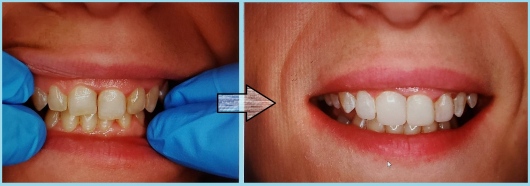

Jestem Amerykaninem, ale mieszkam w Polsce ponad 10 lat. Zajmuję się zachowawczą, leczeniem kanałowym pierwotnym i wtórnym pod mikroskopem, protetyką i prostą chirurgią. Wykonuję też Bonding i Flow Injection Technique.